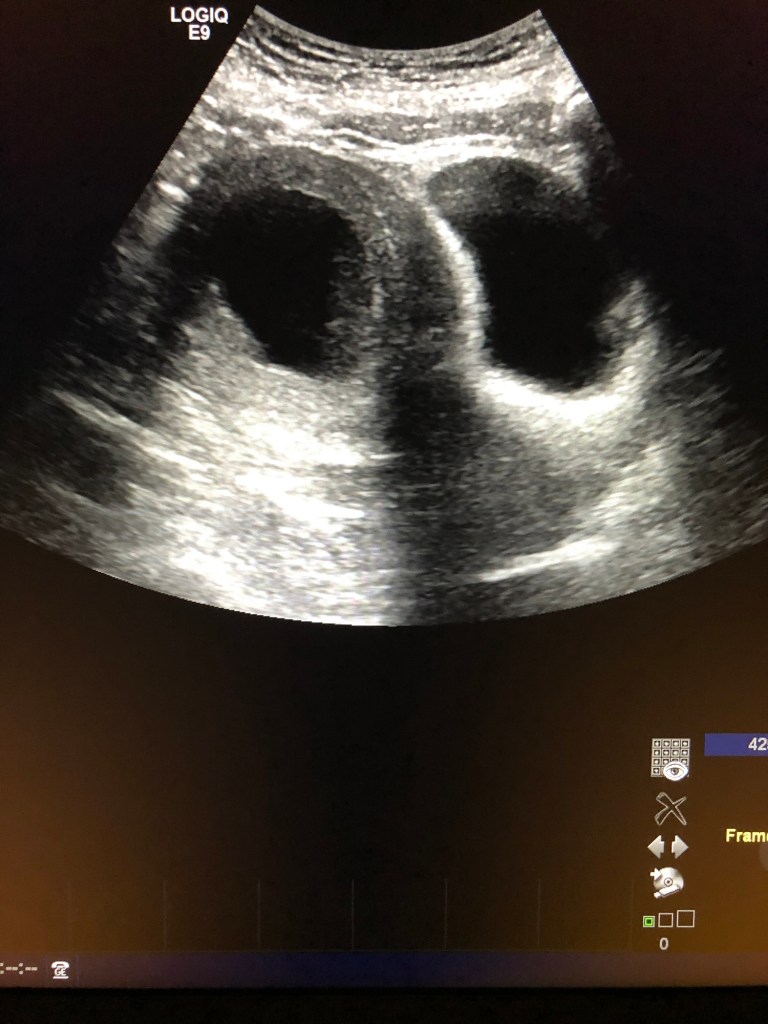

As an ultrasound technologist, I have a hard time understanding why imaging guidance isn’t routinely used. Instead of seeing exactly what is being treated, the physician relies on feel and estimation.

To me, it seems so simple to use ultrasound guidance. To visualize the endometrium. To ensure complete and even ablation. To remove uncertainty.

Imaging could take the guesswork out of the equation.

The ablation I had undergone in 2017 had not been successful.

The inferior portion of my endometrium had been fully ablated.

But the upper portion, near the fundus, remained completely intact.

Open.

Still functioning.

Because the upper portion of the endometrium was still producing menstrual blood, I was still having periods. But the lower portion of the uterus, which normally allows blood to flow out, had been essentially burned shut.

The blood had nowhere to go.